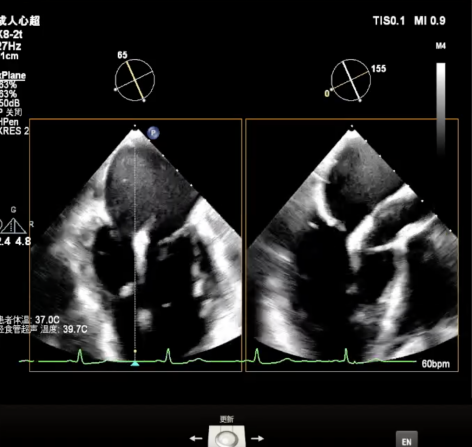

术前超声诊断

X-plane视窗可见二尖瓣瓣叶“连枷样”运动;

3D enface view示二尖瓣内后叶2偏1区瓣尖可见断裂的腱索呈“连枷样”运动,偏心性返流

PISA定量:EROA=1.06cm²,Rvol=145ml,Vmax=399cm/s

PW显示左肺静脉收缩期血流频谱呈逆向

3D模式测量二尖瓣瓣口面积5.62cm²术前TEE房间隔高度约4.72cm